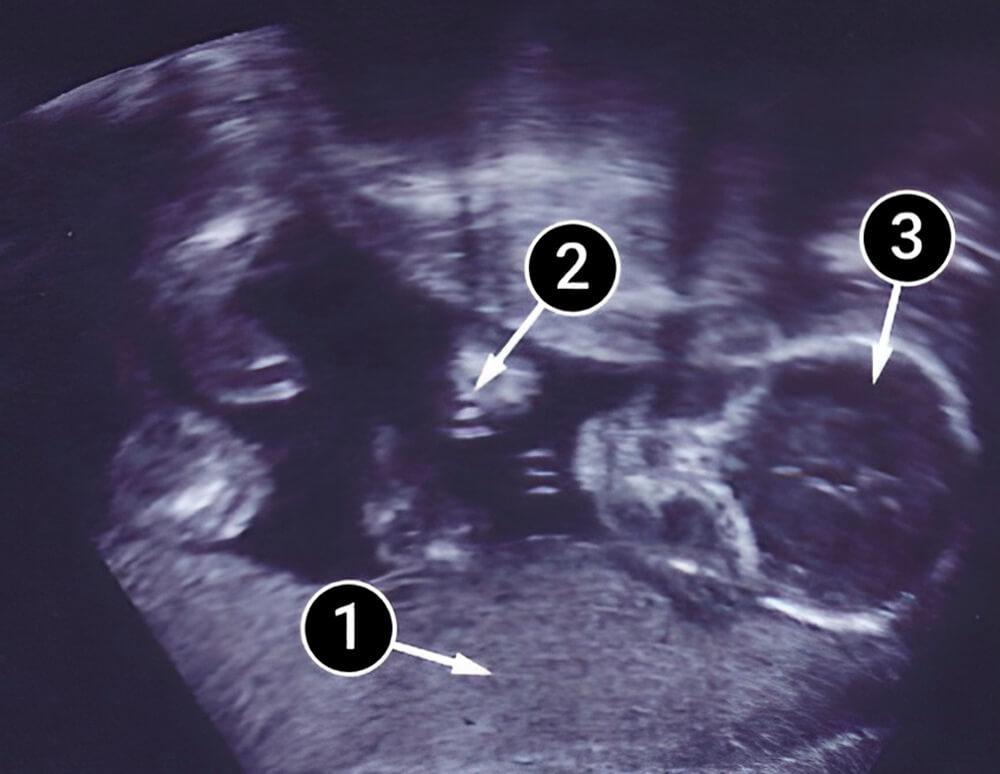

En la siguiente imagen puedes ver gemelos. Uno de ellos se sienta en primer plano mientras que el otro se encuentra un poco más arriba. Los pequeños pies y sus deditos son visibles del bebé en primer plano; mientras que las extremidades del otro bebé son parcialmente distinguibles.

piernas

cabeza